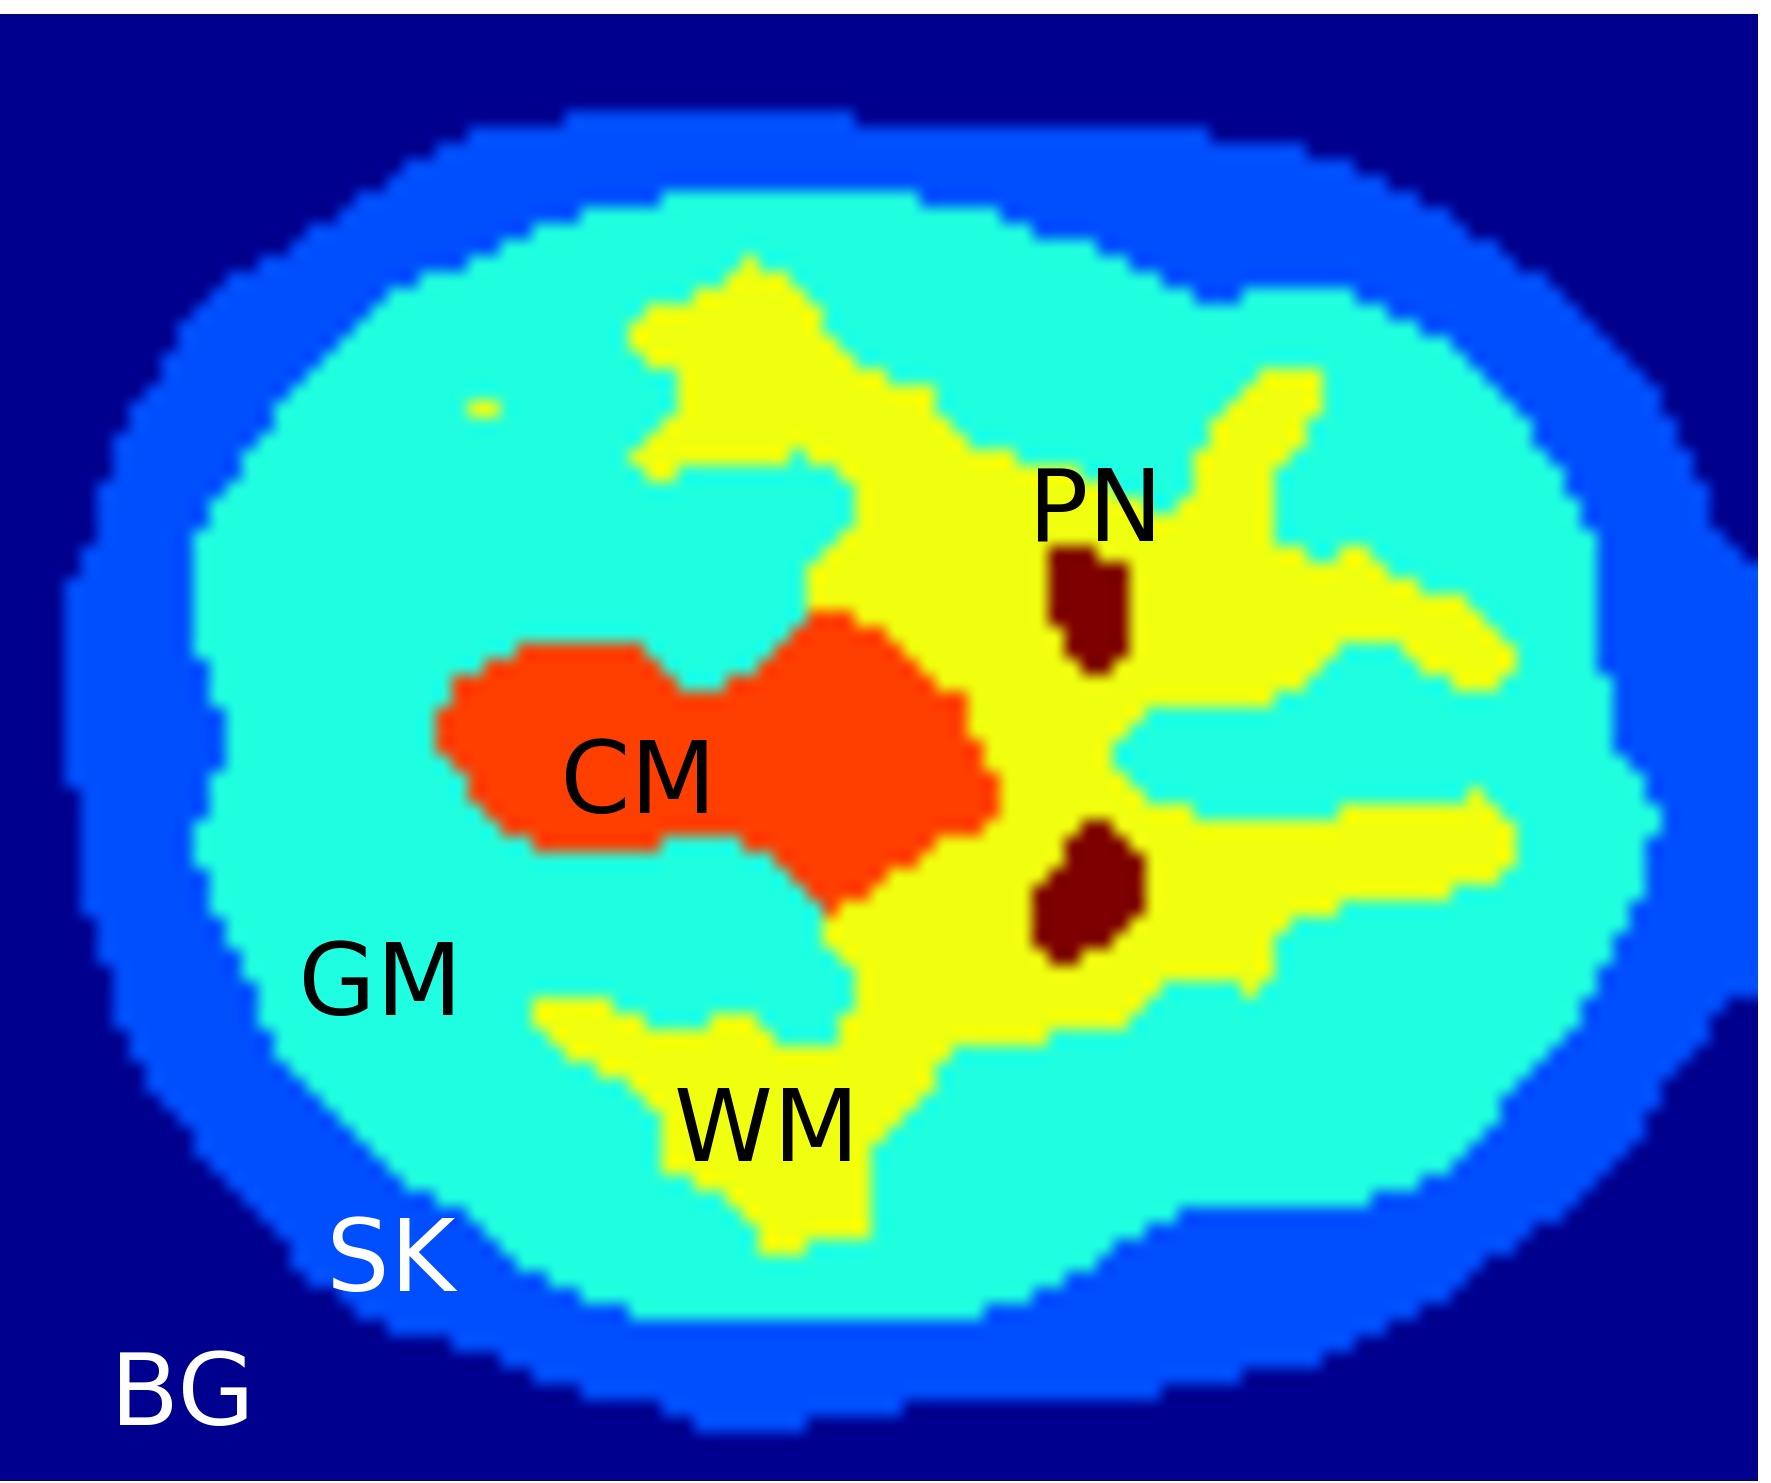

Saad et al. [32] use a kinetic model to devise a multi-class, seed-initialized, iterative segmentation algorithm for molecular image quantification. Due to the low signal-to-noise ratio and partial volume effect present in dynamic-positron emission tomography (d-PET) data, their segmentation method has to incorporate prior knowledge. In this noisy setting, the segmentation of a basic random walker [14] would just result in Voronoi regions around the seed points. A new extension by Saad et al. makes this method usable for noisy data by adding energy terms that account for desirable criteria, such as data fidelity, shape prior, intensity prior, and regularization. In order to attain the superior segmentation quality of the algorithm, a proper choice of weights for the energy mixture is crucial.

To facilitate this choice of weight parameters, their code also provides numerical performance measures that assess the quality of each class. One such measure is the Dice coefficient [9], which gives a ratio of overlap with labelled training data. A second measure expresses an error of the quality of the kinetic modelling. Overall, the algorithm is influenced by factors or parameters. Ten response variables provide the quality measures per class, disregarding background.

Theoretically, the parameter calibration could proceed by numerical optimization of the performance with respect to the weights of the energy terms. However, for instance the Dice coefficients that indicate agreement of the segmented shape with given training data for putamen, using the two configurations of Figure 1(c) and (d), are both above the 90th percentile of the sampled configurations and less than standard deviations apart. Numerically, this means that both segmentations are of the same, near optimal quality. Yet by visual inspection, it is possible to tell that the putamen (PN) shape in (d) is favourable over the one obtained in (c). Hence, guidance of a human domain expert is desirable to visually sort among several candidate solutions in order to find an improved segmentation, which is hard or impossible to choose automatically. An interactive workflow that facilitates such a procedure is subject of Section 5.2.